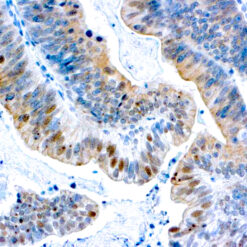

Iba1 (AIF1)

Actin-binding protein that enhances membrane ruffling and RAC activation. Enhances the actin-bundling activity of LCP1. Binds calcium. Plays a role in RAC signaling and in phagocytosis. AIF1 colocalizes with actin, and upon stimulation, translocates to lamellipodia. It is also a marker of human microglia and is expressed by macrophages in injured skeletal muscle. The gene encoding AIF1 resides in the tumor necrosis factor (TNF) cluster of genes, located in the region represented by the human major histocompatibility complex (MHC).

| Cellular Localization | Cytoplasmic and Cell Surface |